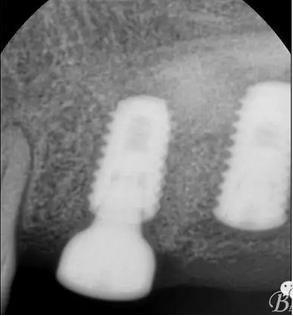

X光片

術(shù)后x光片,右上6直接上愈合基臺(tái),但未完全就位,右下7手術(shù)過(guò)程略

這是術(shù)后1月的片子,重新就位愈合基臺(tái)